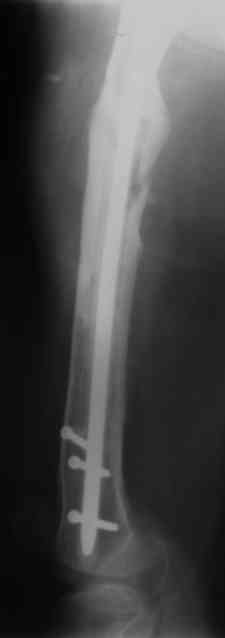

Re: Proximal femoral shaft nonunion + osteomyeliti

Вчера наш пациент был на контрольном осмотре. Вроде все идет нормально. Рентгенограммы от 25 сентября 2007 г. (прошло 5 месяцев после операции) прилагаю.